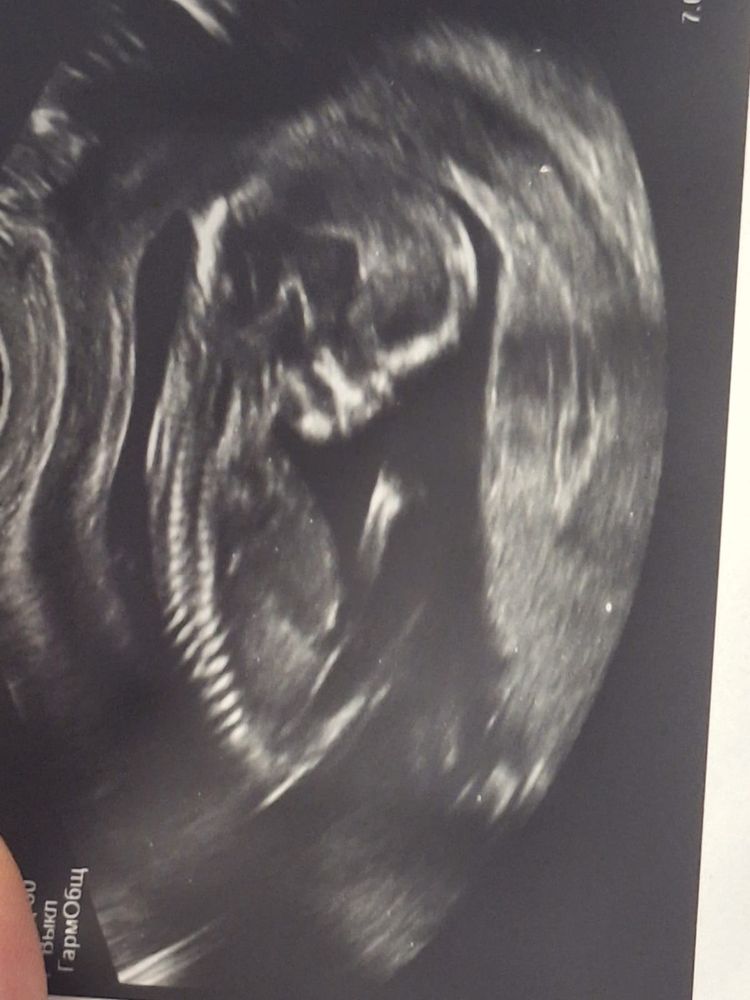

Сегодня мы с малышом прошли свой первый скрининг - все в норме ) Мы уже почти 7 см.

Результаты крови на след неделе только будут )